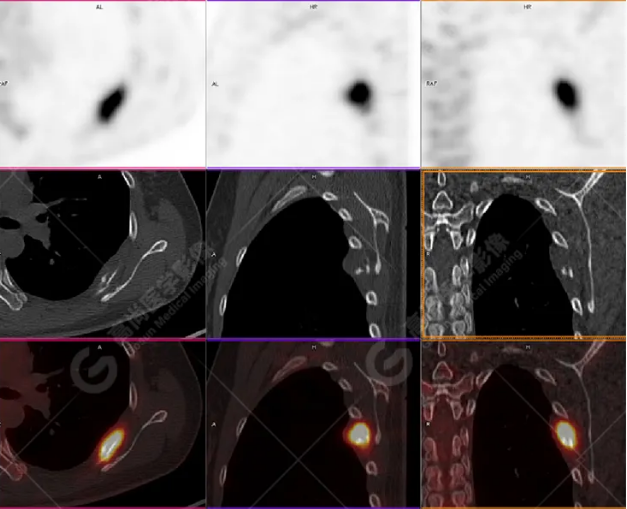

女性 67歲 因背痛查體,糖尿病11年。腫瘤標(biāo)記物:CEA 6.4↑,AFP、CA125、CA199正常。外院MR檢查:胸11椎體-附件左份異常信號,增強環(huán)狀強化,骨原發(fā)?轉(zhuǎn)移?感染?PET/CT影像圖

胸椎溶骨性骨質(zhì)破壞,F(xiàn)DG環(huán)狀代謝增高,SUVmax為4.0。

左側(cè)乳腺一軟組織結(jié)節(jié),F(xiàn)DG代謝增高,SUVmax為2.6。

最終診斷:左側(cè)乳腺癌伴胸椎單發(fā)骨轉(zhuǎn)移。